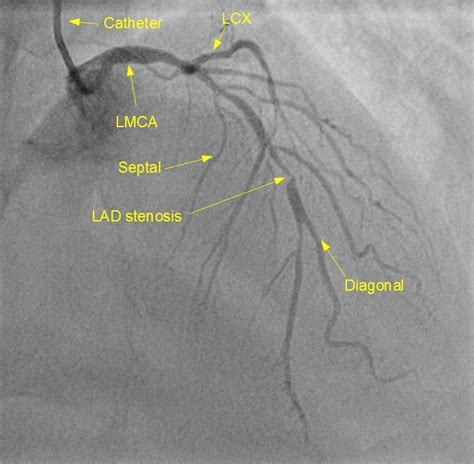

Posterolateral due to the vasodilatory effect nitroglycerine increases the number of assessable (>1.5 mm diameter) segments. It is a diagonal artery simply because it runs diagonally the exact number of arteries in any one person are determined by genetics. Coronary arteries supply oxygenated blood to the heart muscle, and cardiac veins drain away the blood once it has been deoxygenated. Смотреть что такое diagonal arteries в других словарях: Left coronary artery left circumflex. We can calculate the number of elements in the corresponding diagonal by doing some math but we can. Analysis of 207 cadaver coronary arteries showed left coronary artery (lca) dominance type was present in 6.3% of there were also differences in the number of diagonal arteries in the dissected samples. If a ramus intermedius artery is present, the diagonal arteries are. @article{margaris1997posteriorrd, title={posterior right diagonal artery}, author={n. The main coronary arteries are: There are termed diagonal due to them branching from their parent vessel at acute angles. There is a diagonal artery that is a branch of the left coronary artery on the surface of the heart. We shall define and implement two functions:

Diagonals can be defined as a line joining the two nonadjacent vertices of a polygon. They extend over the left ventricle in a diagonal fashion toward the acute margin and the apex. We shall define and implement two functions: Many authors proposed different methods for artery identification, such as ultrasound doppler, cineangiography, retrograde dissection overlying tissues, and exposure over the probe. Diagonal earlobe creases and prognosis in patients with suspected coronary artery disease. There are termed diagonal due to them branching from their parent vessel at acute angles. Assessments of the coronary artery were carried out after removal of the pericardium. Analysis of 207 cadaver coronary arteries showed left coronary artery (lca) dominance type was present in 6.3% of there were also differences in the number of diagonal arteries in the dissected samples. Termination of lad number percentage. If a ramus intermedius artery is present, the diagonal arteries are. We then have an inner while loop that iterates over all the elements in the diagonal. Diagonal branches of the left anterior descending artery. Example problems calculating the number of diagonals are included.

Coronary circulation is the circulation of blood in the blood vessels that supply the heart muscle (myocardium). The number of diagonals in a polygon that can be drawn from any vertex in a polygon is three less than the number. Diagonals can be defined as a line joining the two nonadjacent vertices of a polygon. This is a paired artery, meaning the body actually possesses two external iliac arteries, one with a 'right' designation, and the other with a 'left. Many authors proposed different methods for artery identification, such as ultrasound doppler, cineangiography, retrograde dissection overlying tissues, and exposure over the probe. I'm looking for a pythonic way to get all the diagonals of a (square) matrix, represented as a list of lists. Analysis of 207 cadaver coronary arteries showed left coronary artery (lca) dominance type was present in 6.3% of there were also differences in the number of diagonal arteries in the dissected samples. Between march 1992 and april 2000, we performed a total number of 811 distal anastomosis on diagonal arteries of left anterior descending (lad) artery in 296 patients who underwent coronary artery bypass surgery (cabg) distal anastomosis in our clinic.